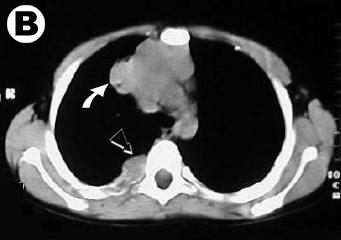

Corte Tomográfico

nivel supra carinal

• Flecha Blanca: la Infiltración mediastinal del tumor sólido con calcificaciones.

• Flecha Negra: Tumor en 4to arco posterior derecho con osteolisis costal.